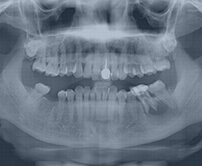

Patient Diagnosis

Endodontist confirms pulp infection via CT and X‑ray before proceeding.